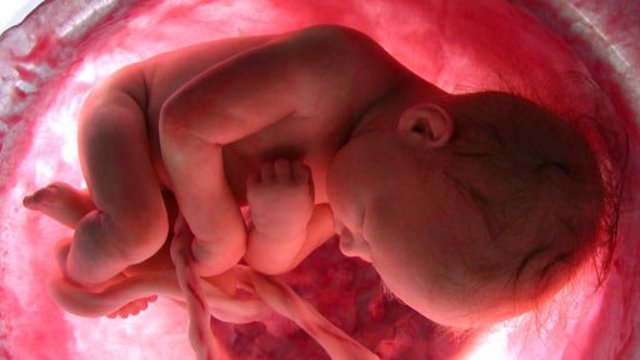

• Semana 28

Semana 28

El feto mide unos 37 centímetros. El cerebro se encarga ahora regular su respiración y su temperatura corporal.

• Semana 30

Semana 30

Se establece la comunicación entre las células nerviosas y el cerebro. La pupila puede distinguir la luz y es capaz de contraerse. En la matriz queda poco sitio y el feto comienza a adoptar la típica posición fetal.